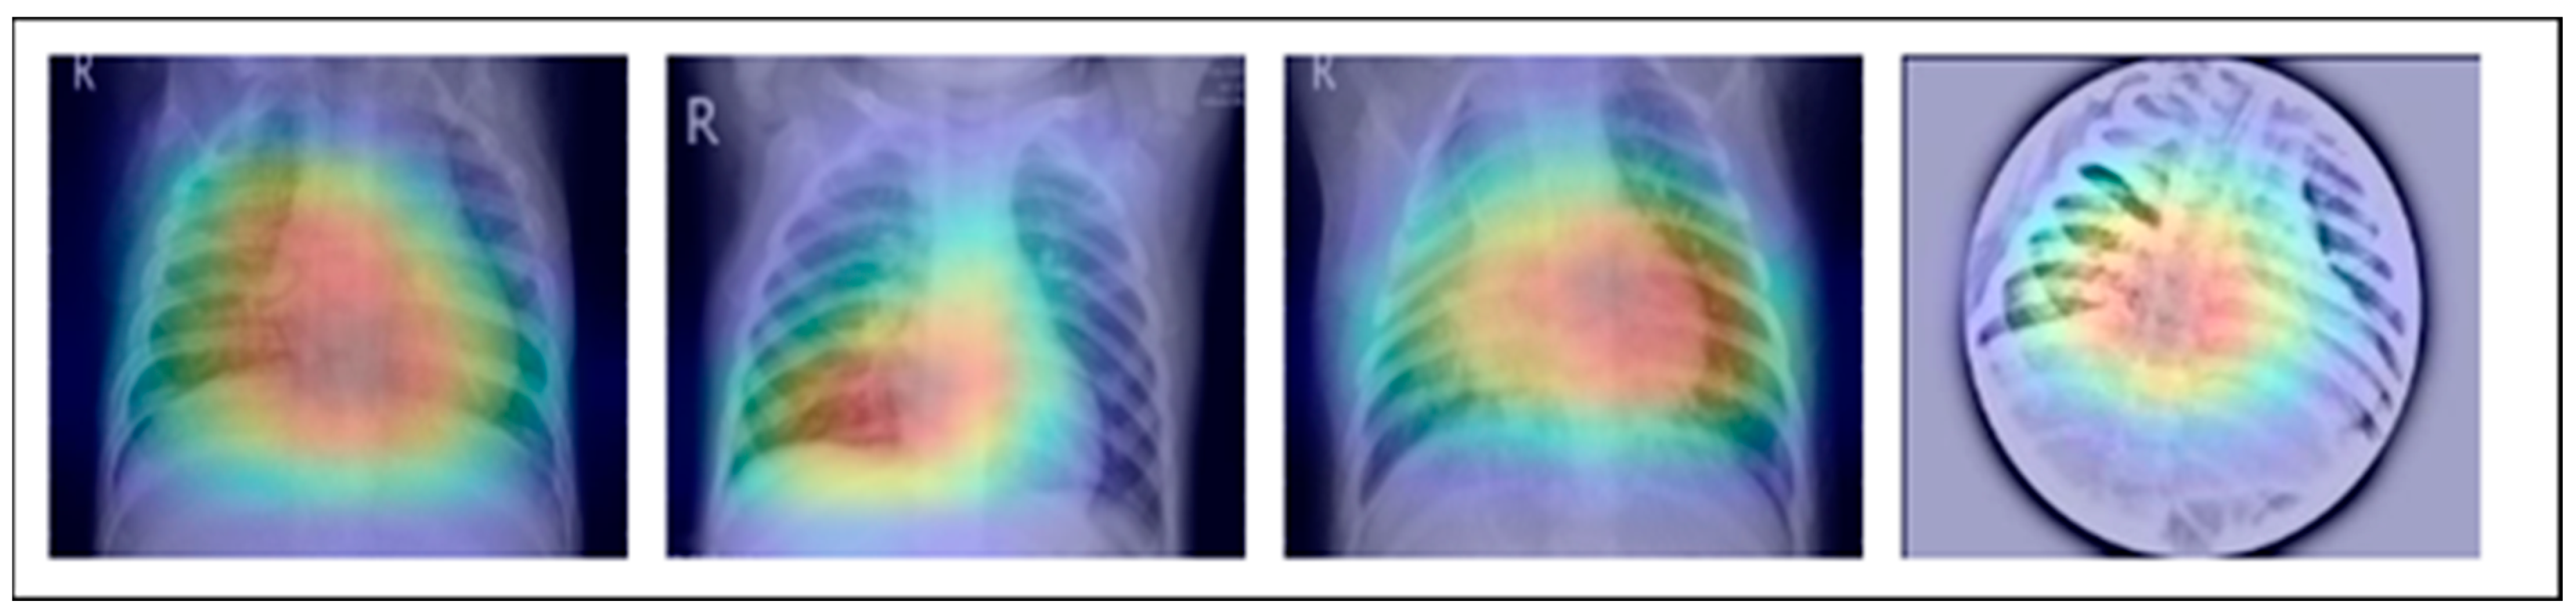

A dataset named Pak-Lungs, which contains 13,313 photos, was used to train and estimate the MixNet-LD model. Images were obtained privately from reputed eye facilities in Pakistan through personal sources. Patients’ and physicians’ permission and willingness to provide data were obtained. It was mutually agreed by the stakeholders that data would be supplied anonymously and that no clinical data would be shared; hence, these conditions kept patient data hidden while making it accessible for study. Both Pak-Lungs and well-known online sources [51] were used as sources for the dataset and the dataset was produced by merging data from numerous Kaggle sources and comprises largely of chest X-ray images associated with various lung illnesses, such as pneumonia, COVID-19, tuberculosis, and normal lung images. The normal and lung disease photos were manually isolated from the dataset acquired by a qualified pulmonologist to construct the training dataset. The pulmonologist detects lung-related traits and establish a standard. The Grad-CAM (gradient-weighted class activation mapping) pre-processing approach marks a major step in improving the interpretability and explainability of deep neural networks, especially in the area of computer vision. Grad-CAM’s capacity to create comprehensible heatmaps that emphasize crucial areas inside an image, together with its ease of use and appropriateness for object localization, makes it an invaluable tool for understanding why a model generates particular predictions. Grad-CAM looks to be preferred above other AI explainability approaches due to its simple implementation, emphasis on localization, ability to provide understandable visuals, and broad use within the deep learning community. While the report does not go into great length about Grad-CAM’s application and rationale, it is clear that this technique was chosen to correspond with the research goals and the requirement for interpretable insights into the model’s decision-making process. Overall, Grad-CAM’s inclusion highlights continuous efforts to improve the transparency and dependability of deep learning models, making them more accessible and trustworthy in many applications, as seen in Figure 3.

Using data from three separate sources, the photos were downsized to a more usual dimension of 700 × 600 pixels in order to simplify and standardize the dataset. Furthermore, during the dataset construction process, experienced pulmonologists contributed to the generation of both lung disease and non-lung disease data for ground truth evaluation. The Grad-Cam technique for image pre-processing was applied to clear the image features and eliminate the interference in the image shown in Figure 2. Using Grad-Cam on the X-ray images enabled us to recognize key regions and ascertain their significance in detecting the existence of pneumonia disease. This technique helps us to identify the distinctive characteristics that greatly influenced CNN’s predictions for the X-ray-based diagnosis of pneumonia pictures.